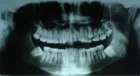

Selective alveolar decortication and periodontal augmentation with a bone graft were the two procedures used for the correction of the skeletal class II malocclusion in the case reported. A 25-year-old male patient presented with a skeletal class II malocclusion with increased bi-maxillary dento-alveolar protrusion, increased overjet, deep bite and imbricated and rotated mandibular incisors with bilateral presence of supernumerary teeth in the maxillary right and left premolar regions. Extraction of supernumerary in the maxillary right and left premolar region, and impacted UL5 was done. Pre-adjusted edgewise appliance, Roth’s prescription (0.022x0.028-inch slot), was bonded and a week later full thickness labial and lingual flaps were reflected in the maxillary and mandibular arches. Circumscribed corticotomy cuts was done and subsequently augmented with a bone graft. Orthodontic treatment was commenced immediately after surgery and orthodontic adjustments were performed every 2 weeks. The entire orthodontic treatment was completed in 9 months. Regional acceleratory phenomenon, triggered by the alveolar decortication, was responsible for the rapid correction of the malocclusion and the augmentation with the bone graft provided adequate bone volume for housing the teeth, thereby decreasing the possibility of subsequent relapse.